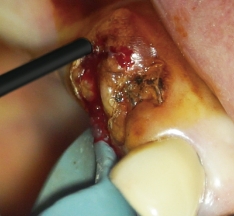

歯髄の焼灼、根管内外の感染組織や汚染物質の焼灼が行え、歯肉切除用のモードを選択することで、電気メスとしても使用可能です。

高周波通電により、チップ電極の先端部と接触した部位を発熱させることで、組織の焼灼・凝固・切開を行うことができます。

根管長測定機能によって根管内のチップ電極の位置を設定し、フットスイッチを踏むことで1秒間のHFCが行えます。